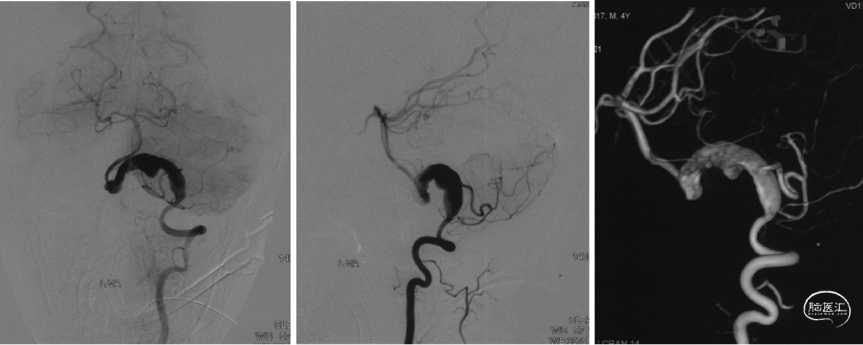

脑血管造影

脑血管造影显示左椎动脉巨大血栓化蛇形动脉瘤,累及小脑后下动脉(PICA)。